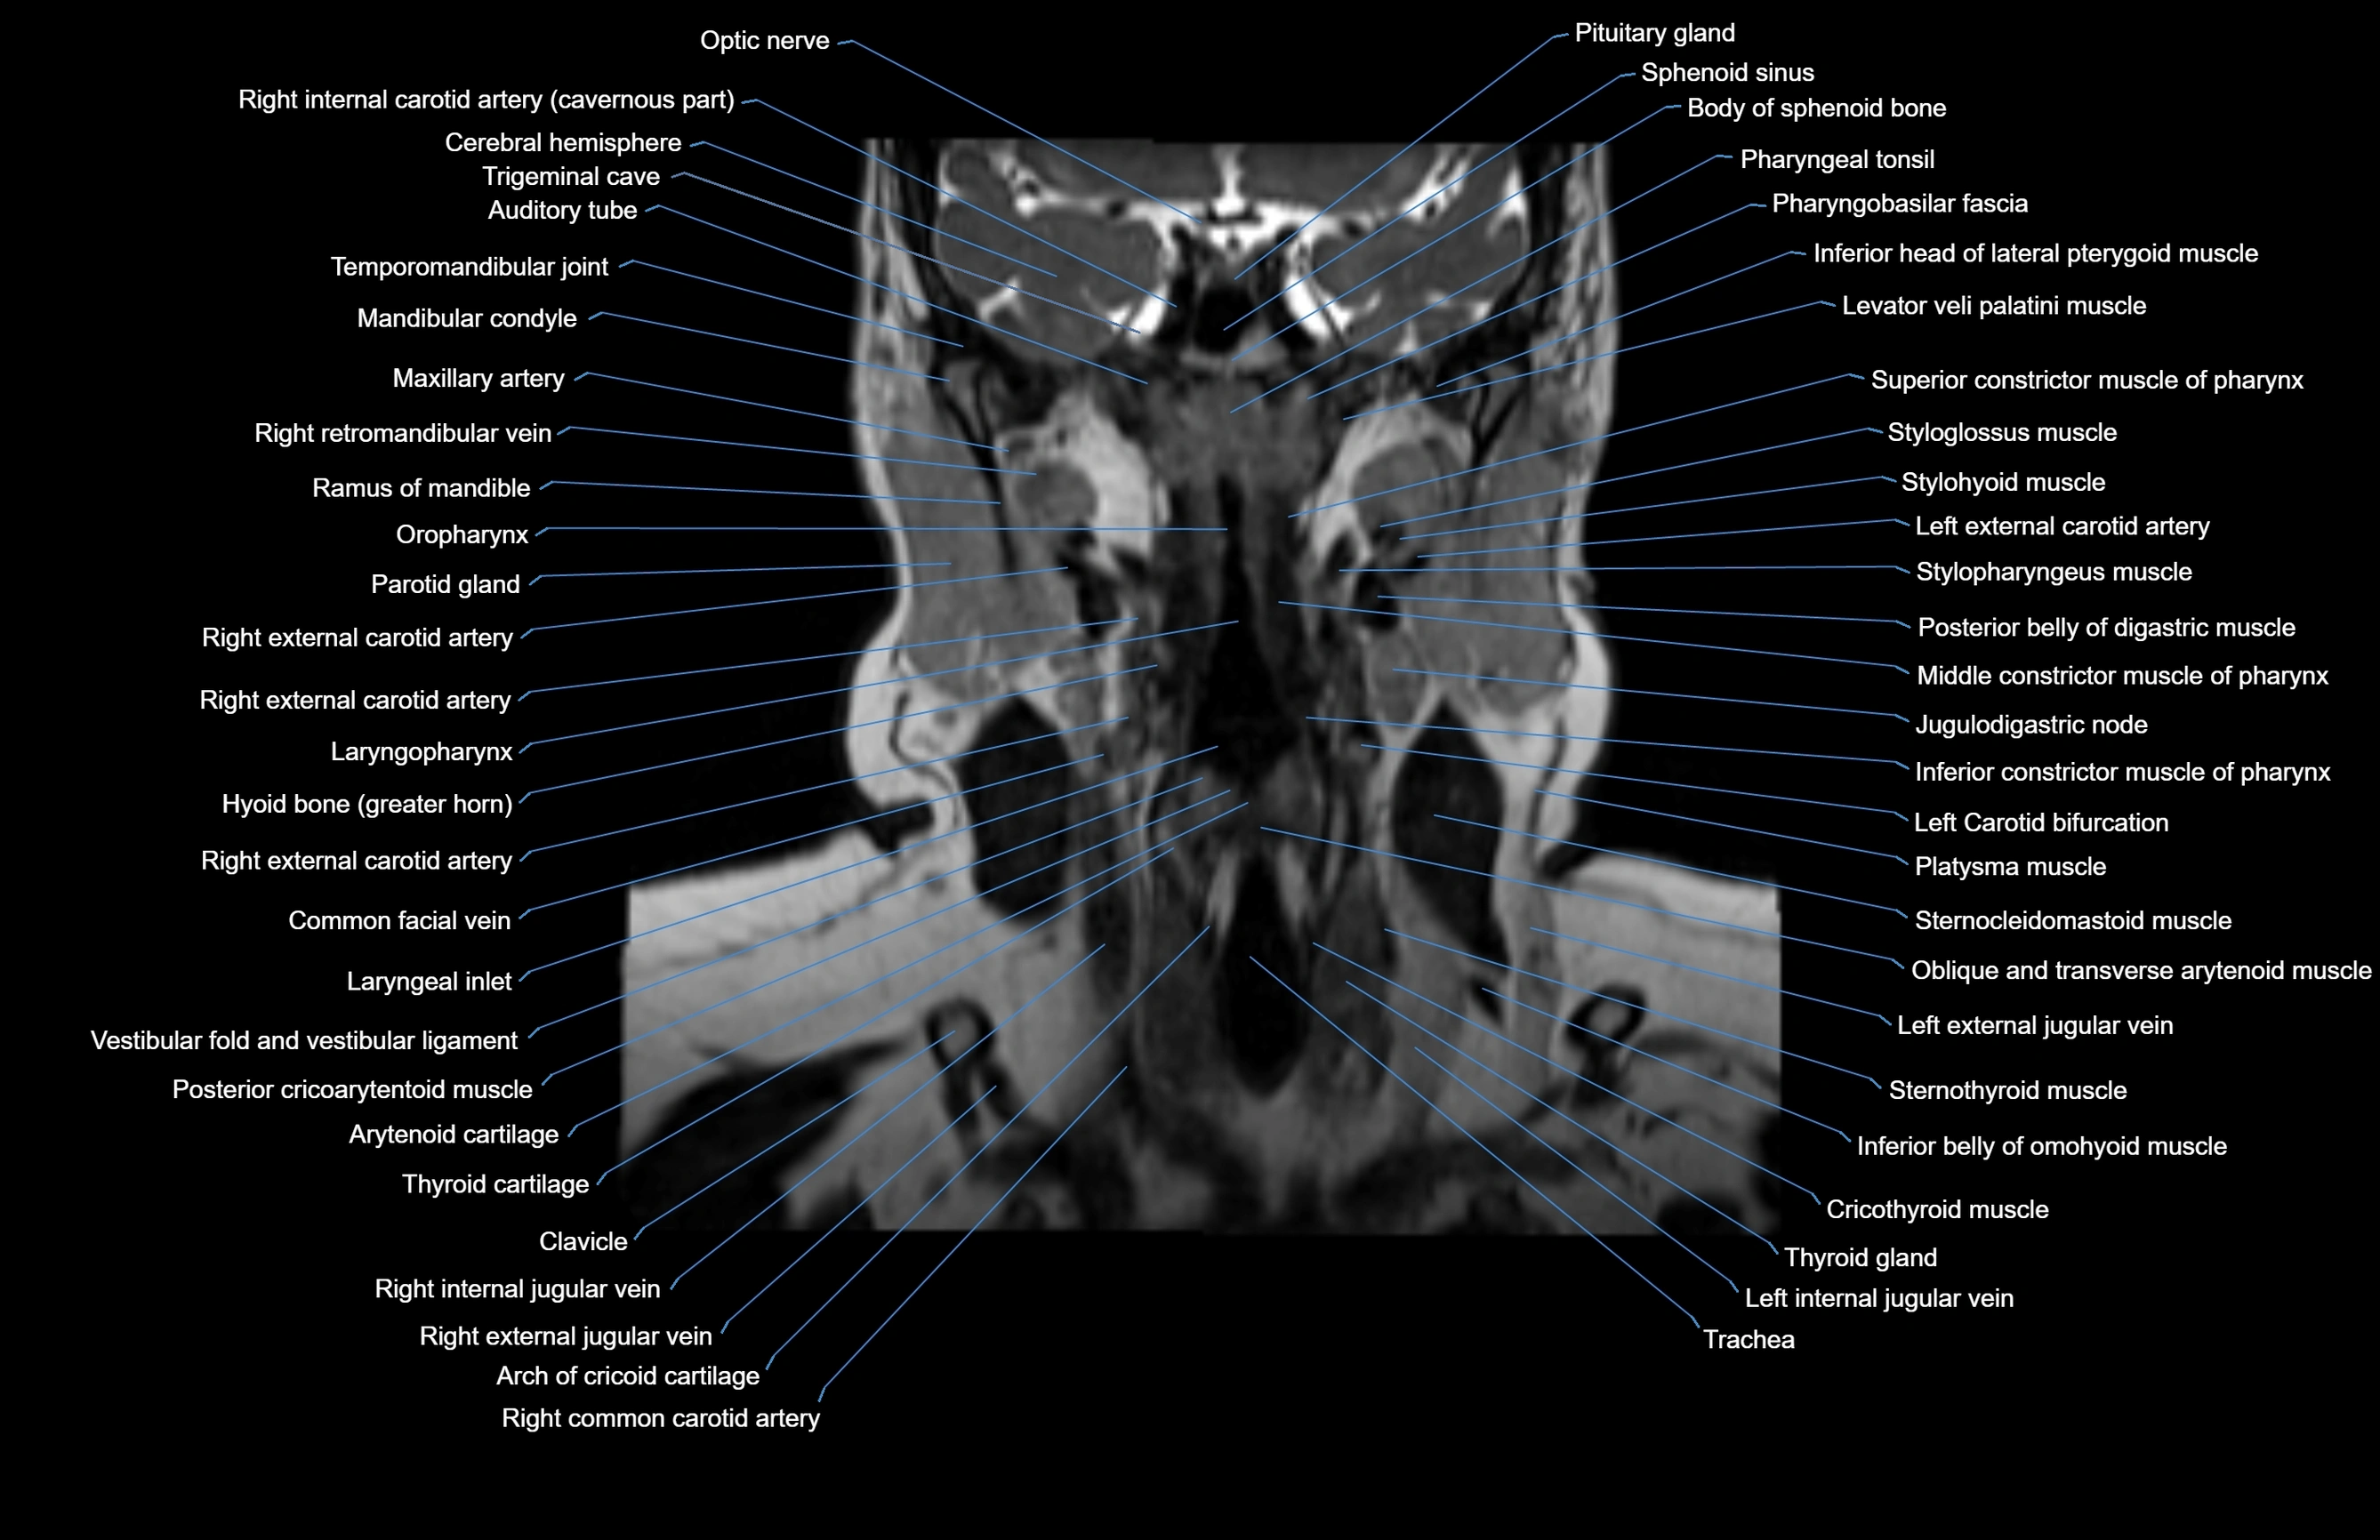

MRI images